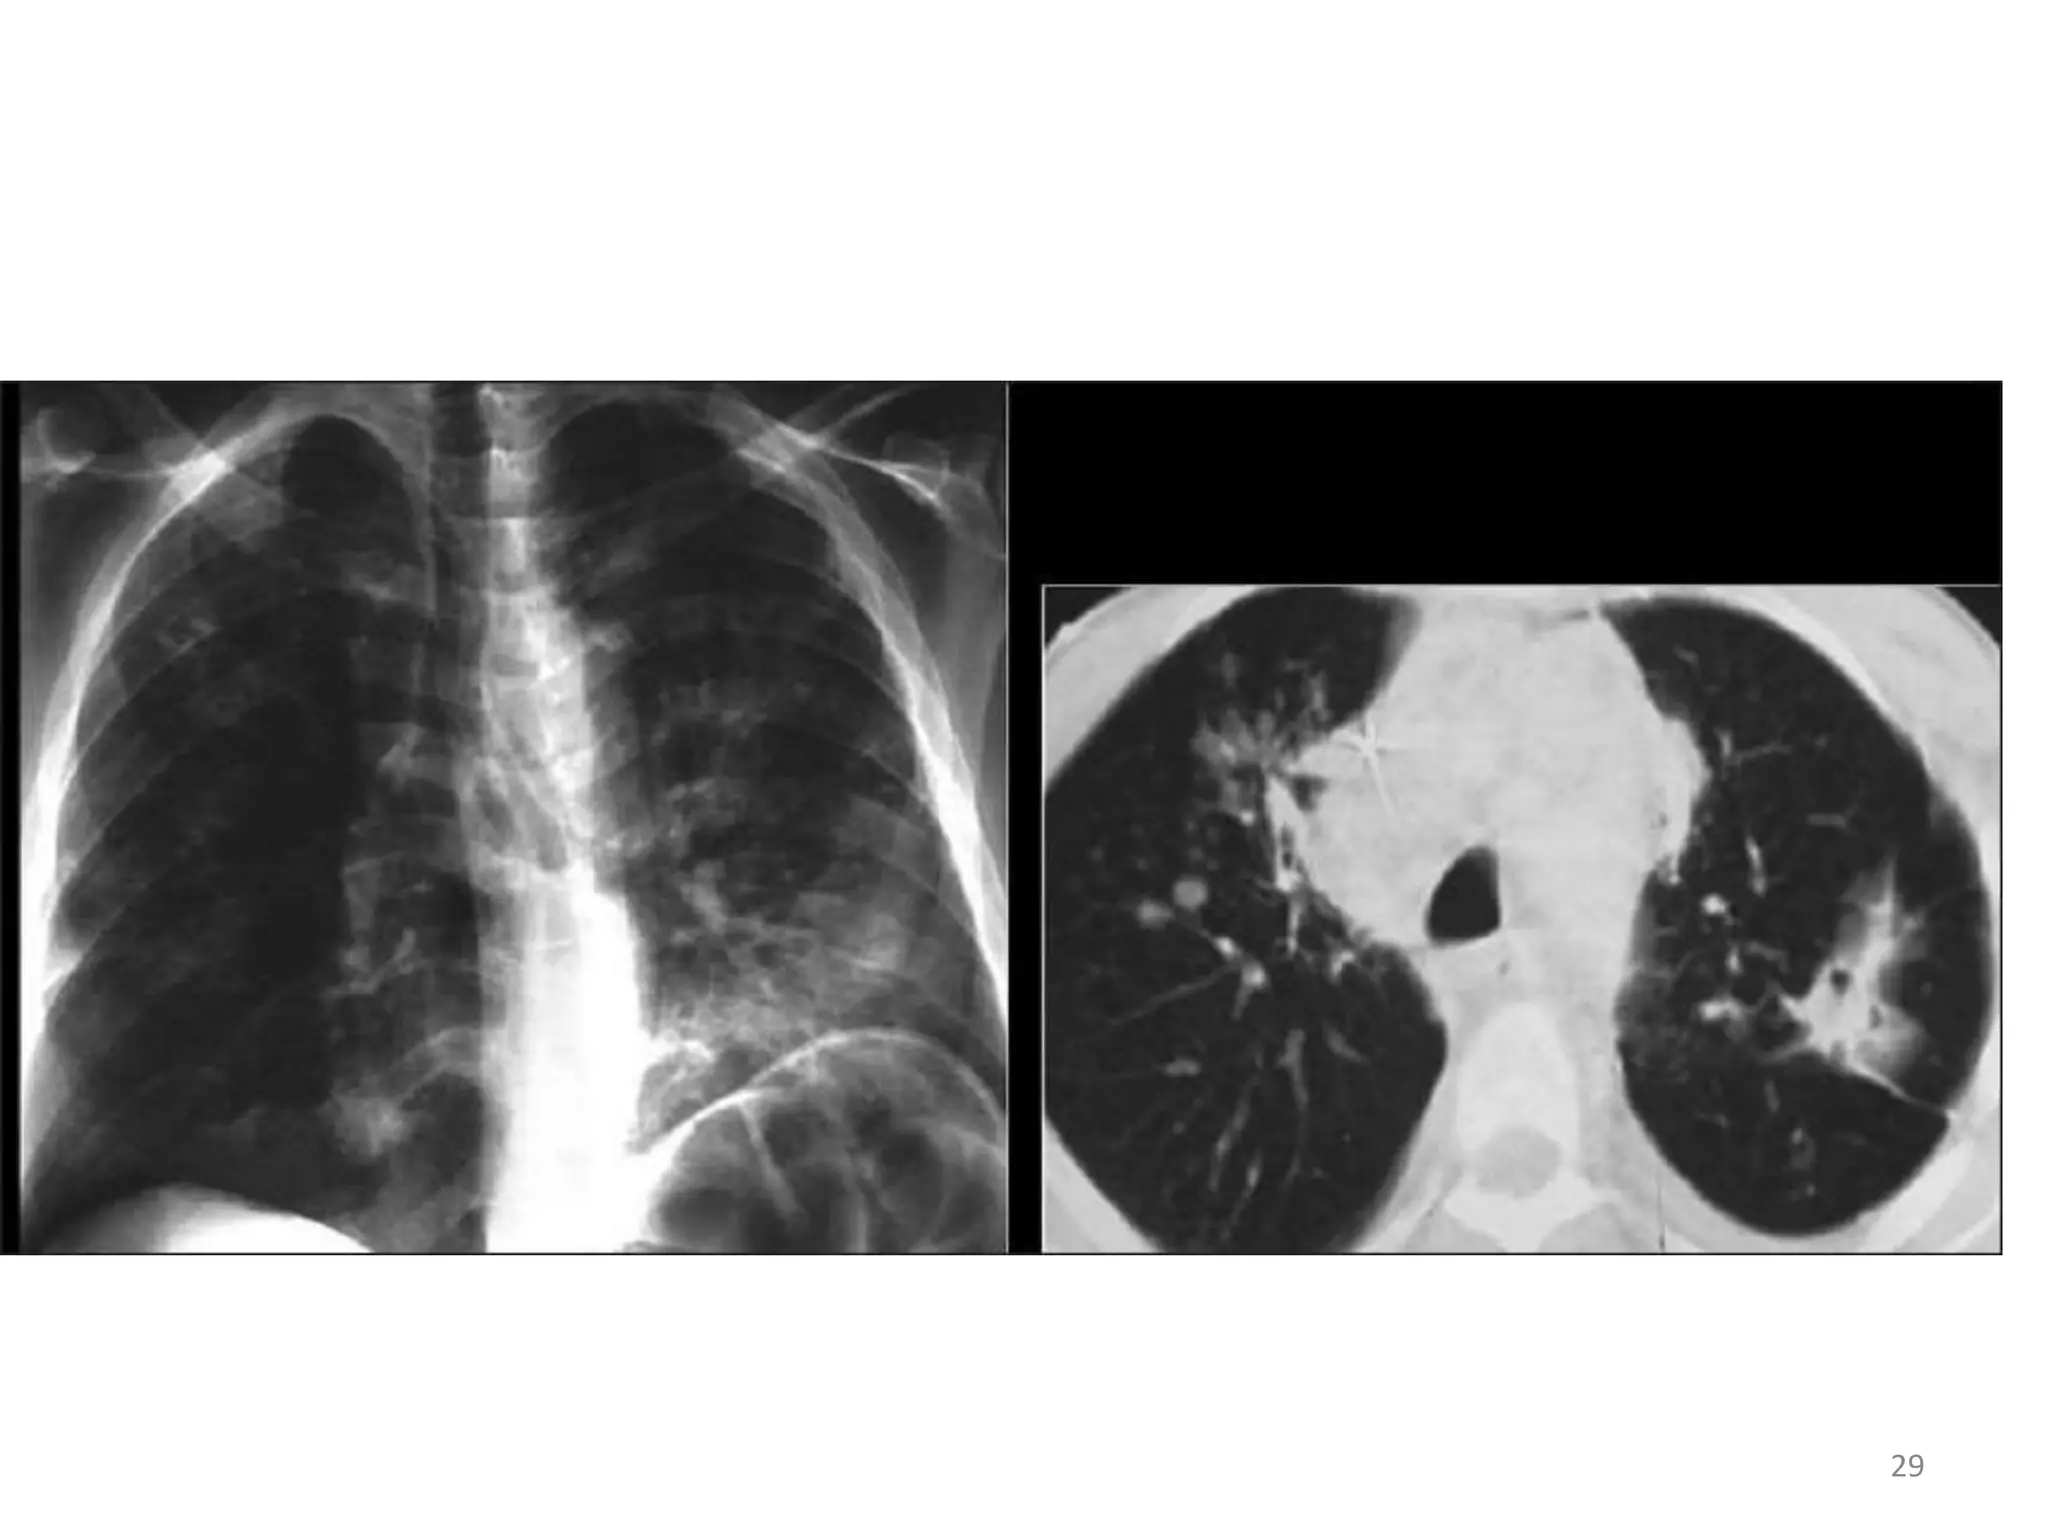

• common presentation is disseminated disease

with fever, weight loss, and night

sweats,abdominal pain, diarrhea, and

lymphadenopathy.

• Bilateral, lower lobe infiltrate suggestive of

miliary spread.

• Alveolar or nodular infiltrates and hilar and/or

mediastinal adenopathy can also occur.

• Anemia and elevated liver alkaline phosphatase

are common.

24

• #26 focal consolidation CXR (left), diffuse patchy infiltrates and cavities (right). The features resemble Mycobacterium tuberculosis ,nonspecific and the diagnosis is often delayed